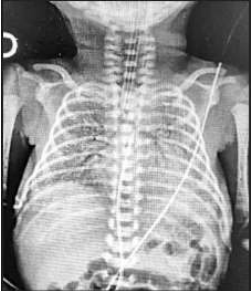

RN nasceu de parto vaginal, com APGAR 5 e 6, apresentando desconforto respiratório de imediato, caracterizado

por gemência, tiragem subcostal e taquipneia. A idade gestacional pela DUM foi de 31 semanas. RN foi levado à UTI

neonatal, com piora importante do desconforto respiratório, necessitando de intubação orotraqueal. Neonatologista

solicitou RX de tórax (imagem abaixo). Genitora relatou perda de líquido vaginal um dia antes do parto, porém,

II. A prematuridade e o padrão radiológico tornam a Síndrome do Desconforto Respiratório um dos principais diagnósticos desse paciente.